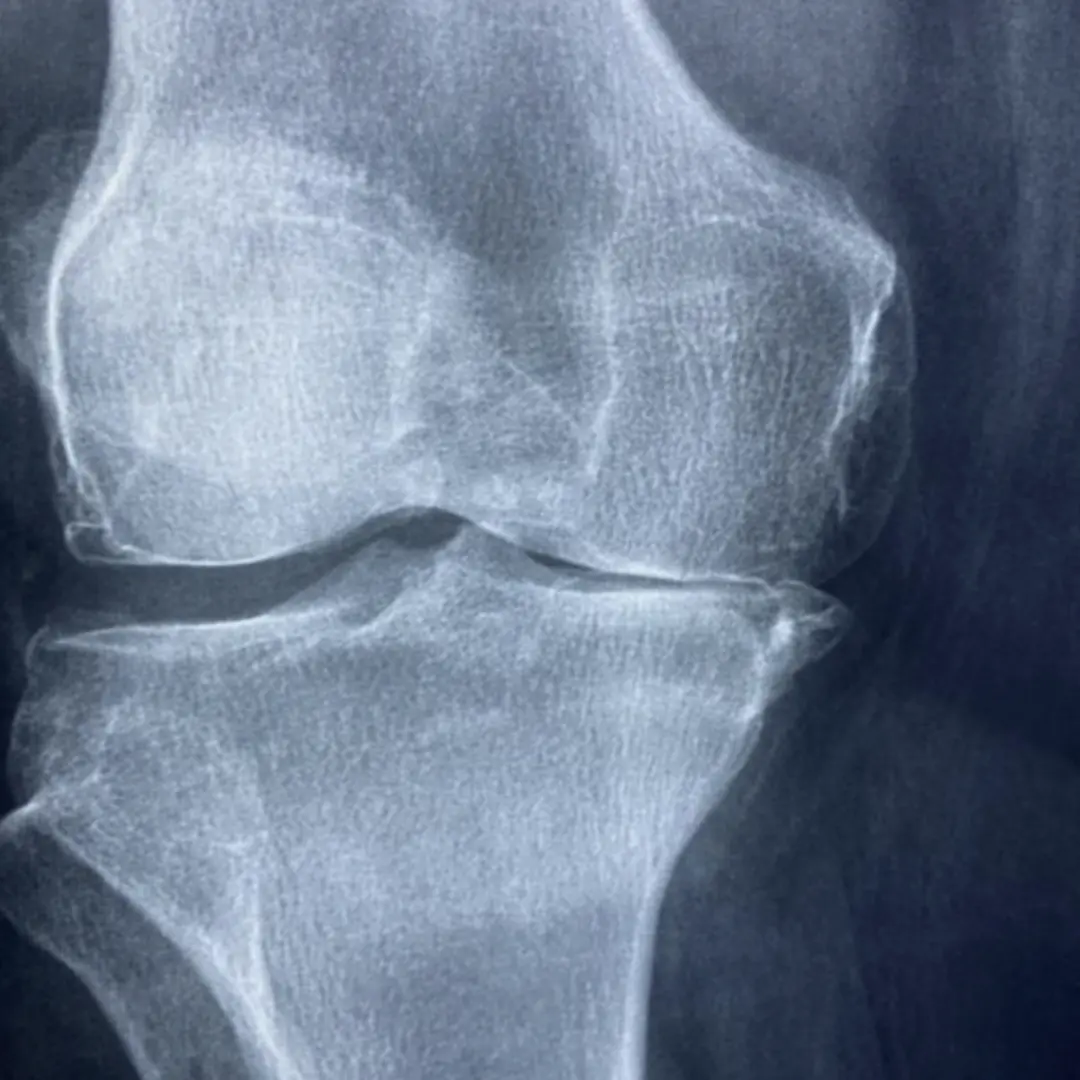

퇴행성 관절염은 가장 흔한 관절염으로, 주로 관절 연골의 손상으로 인해 발생해요. 초기증상은 연골이 닳기 시작하면서 나타난답니다.

- 노화: 가장 큰 원인이에요. 나이가 들면서 관절 연골의 재생 능력이 떨어지고, 연골 자체의 탄성도 줄어들어 점차 손상되기 시작한답니다.

- 외상 및 부상: 과거에 관절 부위를 다치거나 골절된 경험이 있는 경우, 해당 관절에 퇴행성 변화가 더 빨리 나타날 수 있답니다.